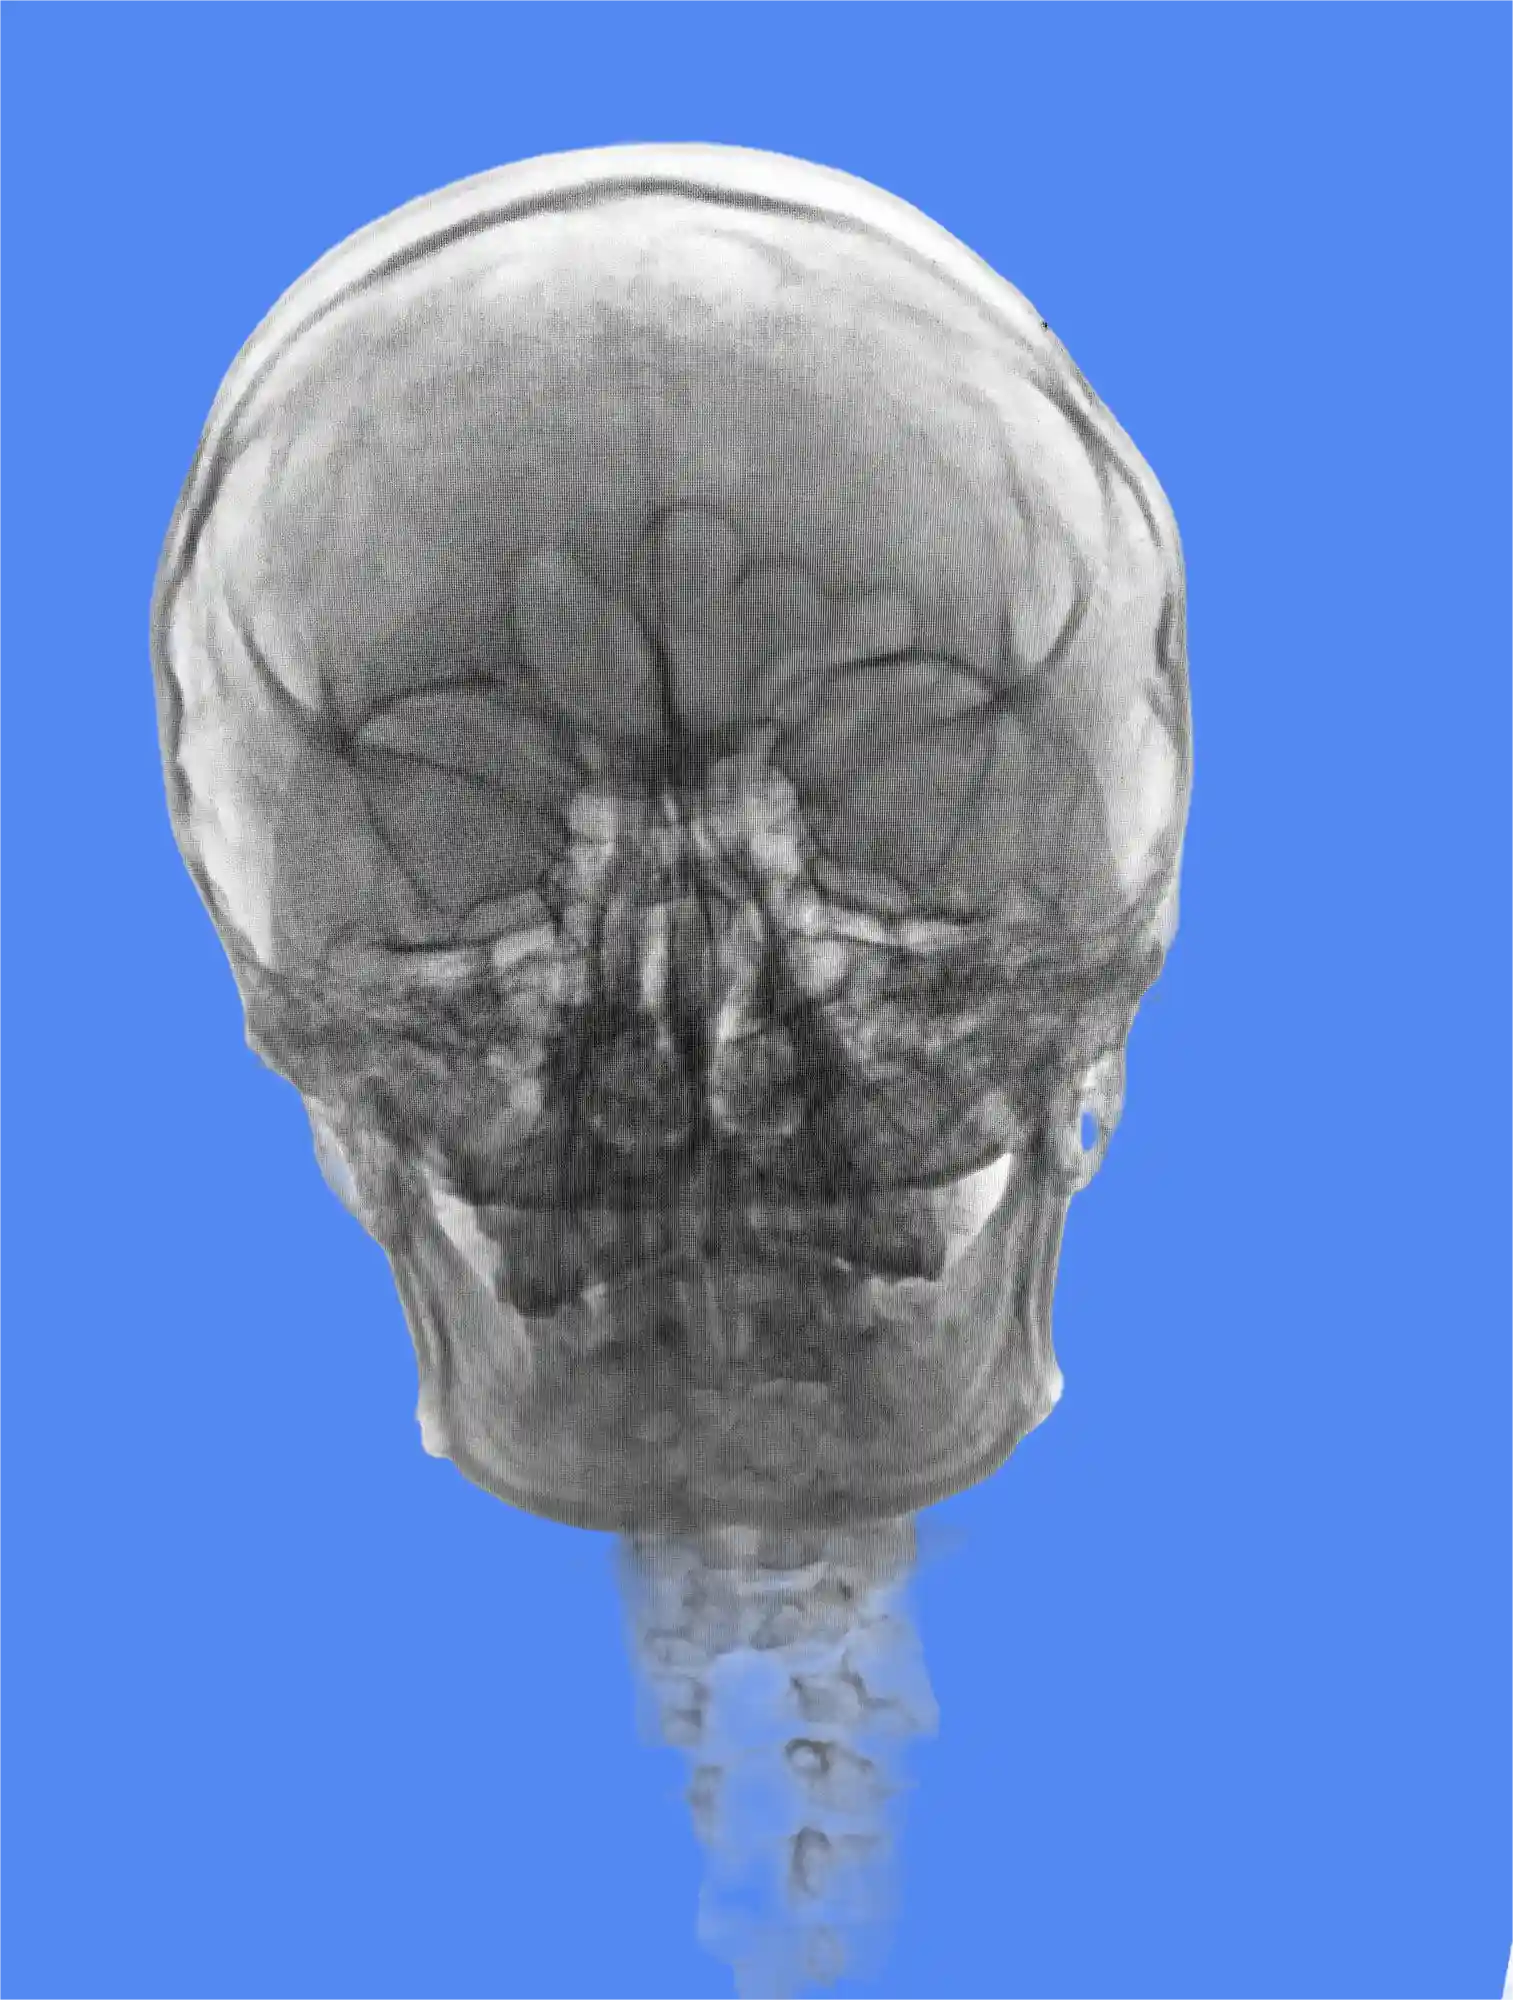

Le rôle de l'hypertension intracrânienne idiopathique IRM

Pour confirmer le diagnostic, les médecins s’appuient sur l’imagerie médicale. L’irm d’une hypertension intracrânienne idiopathique est l’examen de référence.

L’IRM permet d’éliminer d’autres causes graves, comme une tumeur, un caillot sanguin ou une malformation. Elle met également en évidence des signes indirects de la pression, tels que la compression de l’hypophyse (syndrome de la selle turcique vide) ou la dilatation des gaines des nerfs optiques.

Cet examen est totalement indolore. Il garantit un diagnostic précis et sécurisé, étape indispensable avant d’entamer le moindre traitement.